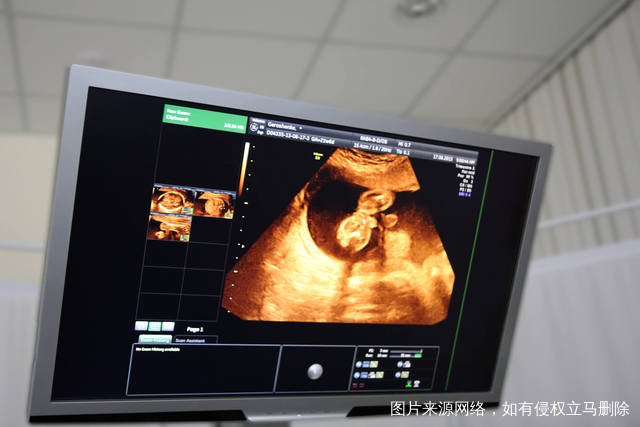

德州市人民医院试管婴儿水平如何?

在全国范围内,如果大家要选择德州市人民医院试管婴儿的话,你会发现这里的试管婴儿水平绝对也算得算是非常不错的,因为这里有良好的诊疗专家坐诊,而且这里的口碑确实也非常好,所以也正因为如此,一直以来试管婴儿成功率都在短时间内逐渐上升。如果要选择试管婴儿这项手术的话,那么建议大家在选择手术的时候最好能够提前和医生进行沟通。